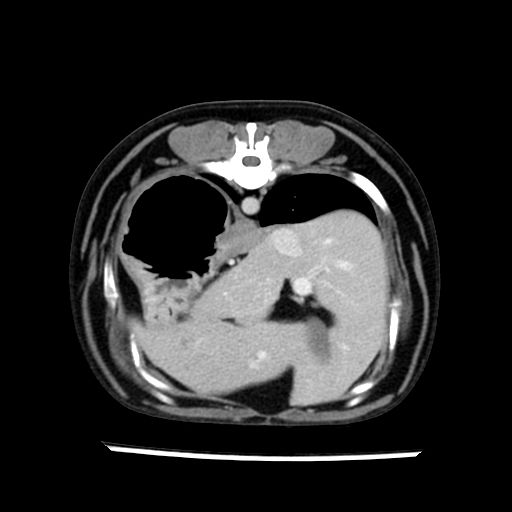

prescritto esame TAC

sequenza immagini limitata al fegato reni e surreni

le immagini ecografiche rispetto alla tac datano circa 7 mesi prima ,le surrenali sono normali nonostante il test acth sia risultato positivo .all’esame TAC dopo diversi mesi risultano aumentate armonicamente nel volume e si individua un forte sospetto di adenoma ipofisario .

sospetto adenoma ipofisario vs. meno probabilmente meningioma della base; intertiziopatia polmonare; lesione espansiva epatica, verosimilmente del lobo laterale sinistro, di sospetta natura neoplastica; lesioni spleniche di natura da definire; iperplasia/ipertrofia delle ghiandole surrenali, bilateralmente; vertebra di transizione del rachide toracico; tenosinovite cronica del muscolo bicipite brachiale di destra.